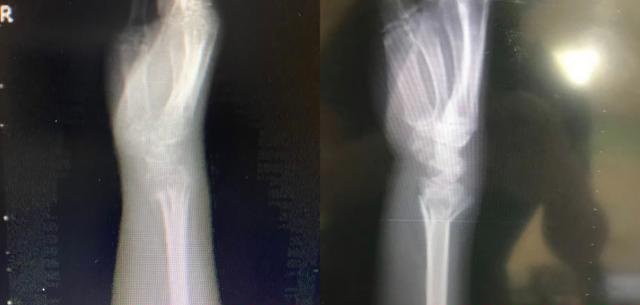

肖医师仔细查看了王阿姨的相关影像资料,惊奇地发现她的损伤部位、损伤类型和自己妈妈之前的骨折情况一模一样。

之前肖医师的母亲不慎摔倒,倒地时右手撑地,当即出现右腕肿胀、畸形和疼痛,拍片即显示右桡骨远端骨折,随后在急诊手法复位并石膏固定4周。

由于及时复位固定和“康复治疗师儿子”的有效康复介入,拆除石膏后,X片复查显示骨痂形成。随后又开始右腕部分负重练习。